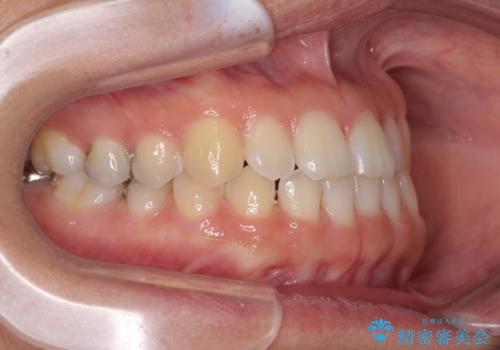

前歯の隙間を閉じたい 短期間でのワイヤー矯正

- 上の前歯の隙間を気にして来院された患者様です。

下の前歯が上の前歯を突き上げるように咬合するため、咬み合わせの位置を改善しながら隙間を閉じていきました。

元々の歯並びが悪くなかったため、9ヶ月で綺麗に仕上がりました。